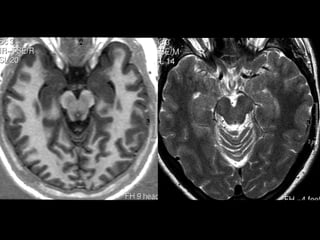

Anatomia cerebral

Gânglios da Base

• Tecido de substância cinzenta sub cortical

simétrico, localizados nas superfícies inferiores

dos hemisférios cerebrais.

• Núcleos lenticulares ( putamen e globus pálido),

núcleo caudado, claustro e amígdala.

Núcleos lenticulares.

• Biconvexo , envolto por substância branca,

• Cápsula externa ( separa do Claustro ),

• Cápsula Extrema ( separa claustro da ínsula ),

• Cápsula interna ( braço anterior , joelho e

braço posterior ).

• Putamen ( lateral , maior e mais escuro ) / globo pálido.

Núcleo caudado.

• Cabeça , corpo e cauda ,

• Cabeça é a principal parte , situada

adjacente ao corno frontal do VL.

• Separado incompletamente do n.

lenticulares pelo braço anterior da cápsula

interna ( feixes de Probst ).

• Cauda postero externo ao tálamo.